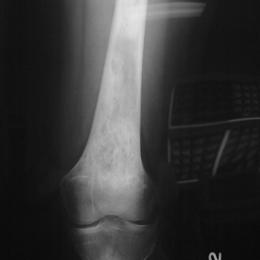

12A)Plain Radiograph Of Epithelioid Hemangioendothelioma Of Femu (1)

Radiographic imaging is used to help form a diagnosis. These include X-Ray, MRI, CT and Bone Scans

An example of an X-Ray is shown.